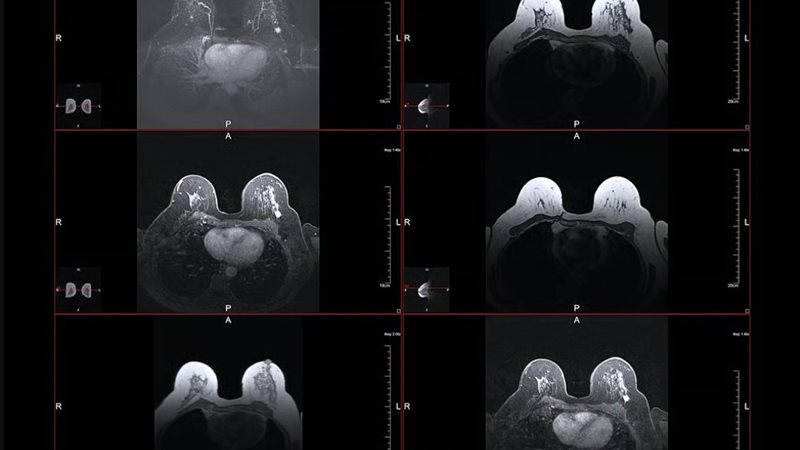

تشير أبحاث حديثة إلى أن فحص الماموجرام الروتيني، الذي يُستخدم عادة للكشف المبكر عن سرطان الثدي، قد يساهم أيضًا في رصد مؤشرات مبكرة لأمراض القلب، والتي تُعد السبب الرئيسي للوفاة بين النساء.

أظهرت دراسة نُشرت في 9 مارس في المجلة الأوروبية لأمراض القلب أن استخدام تقنيات الذكاء الاصطناعي في تحليل صور الأشعة للثدي يمكن أن يساعد في اكتشاف ترسبات الكالسيوم في الشرايين التي تمر عبر أنسجة الثدي. وتُعرف هذه الترسبات باسم تكلس الشريان الثديي، وقد تؤدي إلى تصلب الأوعية الدموية، وهو ما قد يكون مؤشرًا مبكرًا على الإصابة بمشكلات في القلب.

اعتمد الباحثون في الدراسة على تحليل أكثر من 120 ألف صورة أشعة للثدي باستخدام تقنيات الذكاء الاصطناعي، حيث قامت هذه الأنظمة بقياس مستوى ترسبات الكالسيوم بدقة داخل الشرايين.

اعتمدت الدراسة على تحليل صور الأشعة لحوالي 74 ألف امرأة تلقين الرعاية الصحية في مركز إيموري للرعاية الصحية في مدينة أتلانتا، بالإضافة إلى ما يقرب من 50 ألف امرأة في مؤسسة مايو كلينك.

وباستخدام الذكاء الاصطناعي، قام الباحثون بتصنيف ترسبات الكالسيوم في الشرايين إلى أربع درجات، تبدأ من عدم وجود ترسبات وتنتهي بوجود ترسبات شديدة. ثم تمت متابعة المشاركات لمدة سبع سنوات في المتوسط لتحديد من منهن أصيبت بمشكلات في القلب.